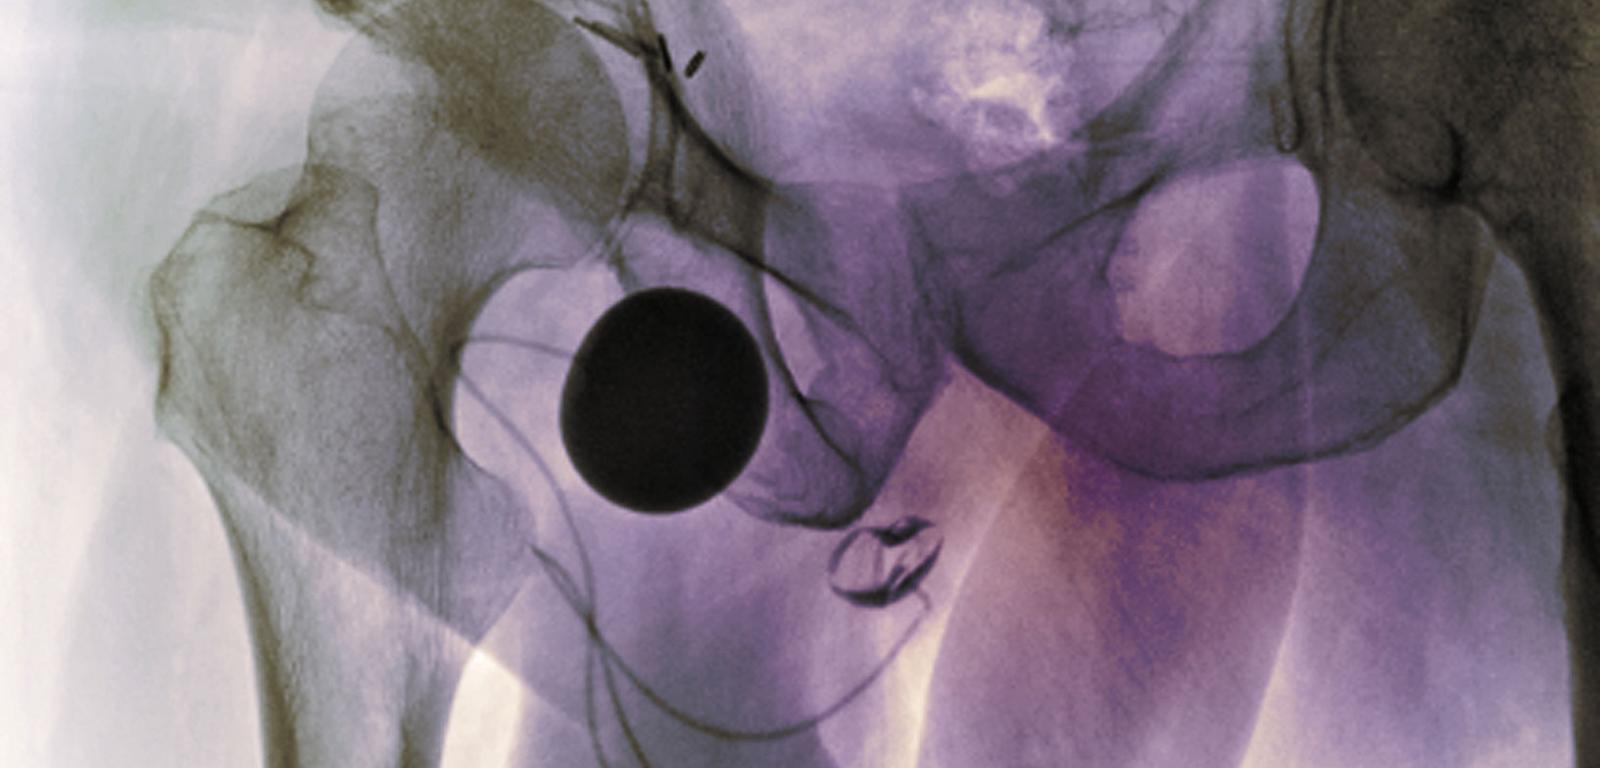

Zdjęcie RTG miednicy. Widać implant kontrolujący oddawanie moczu i zapobiegający jego nietrzymaniu. Zdjęcie RTG miednicy. Widać implant kontrolujący oddawanie moczu i zapobiegający jego nietrzymaniu. Indigo